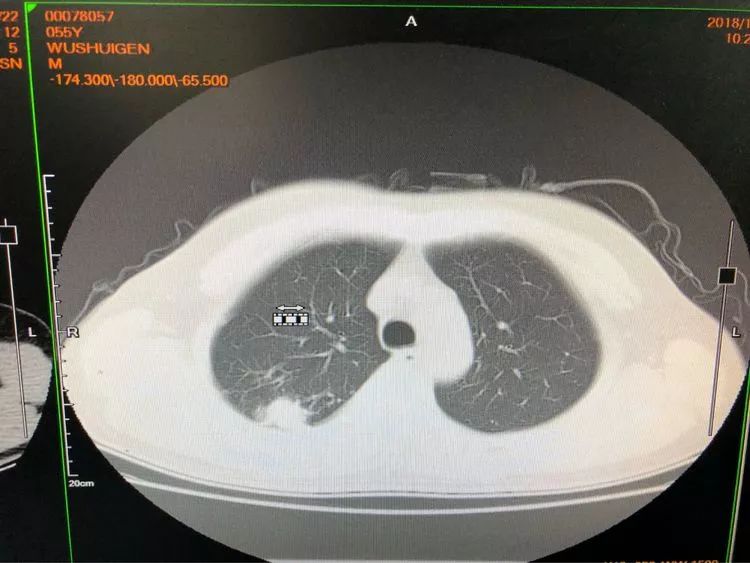

所以,肺穿刺還是很重要的臨床診斷方法。

在這里吳主任要提醒大家:

對于肺部小結節(jié),如果能及早明確診斷,鑒別出惡性病變并及早處理,預后良好,經(jīng)皮肺穿刺可以早期診斷惡性病變早發(fā)現(xiàn),早治療。